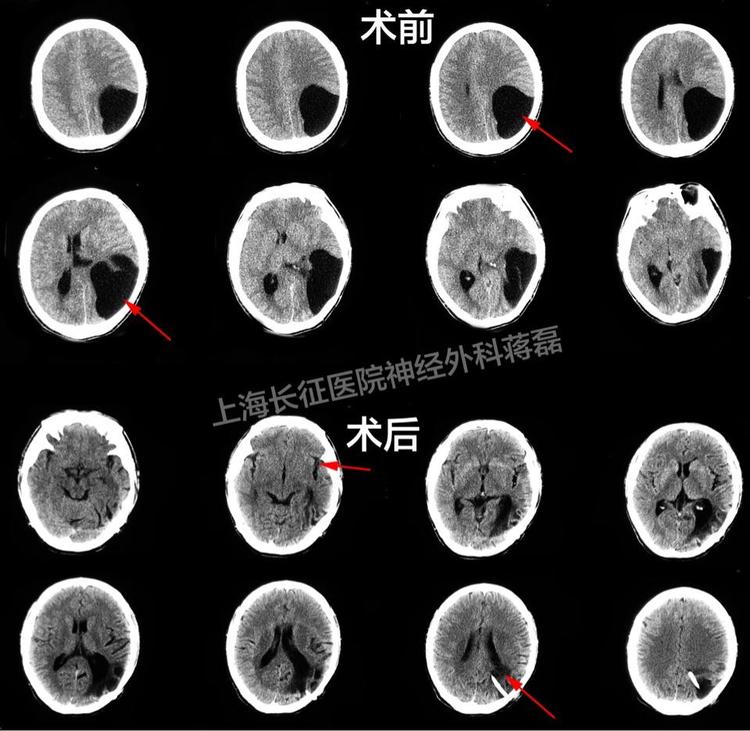

重型对冲性颅脑损伤幕上幕下联合额颞部

640x853 - 77KB - JPEG

750x1000 - 118KB - JPEG

重度颅脑损伤一例

750x432 - 70KB - JPEG